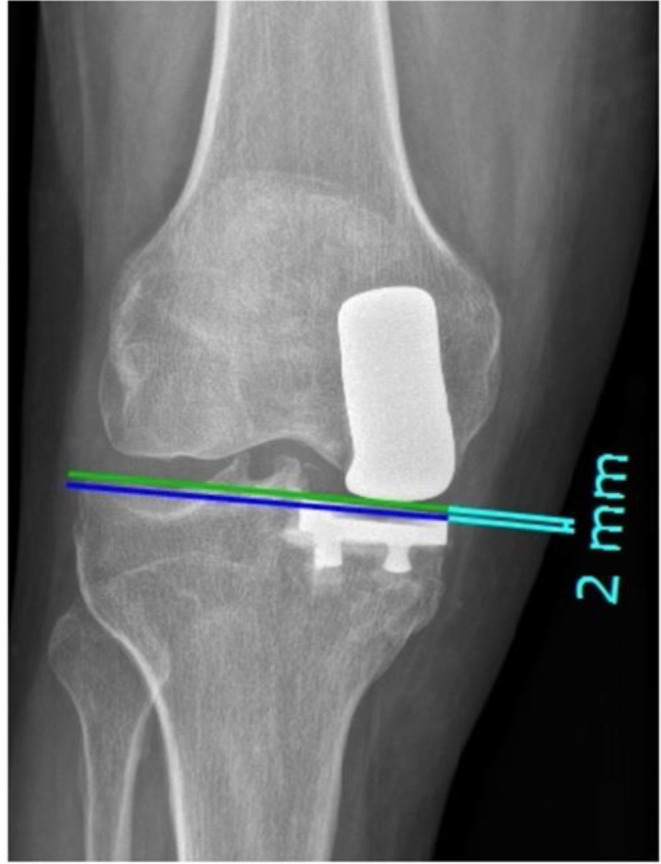

Methods: This retrospective study analyzed 63 patients with cemented medial UKAs with a minimum follow-up of five years. Patient-reported outcomes (PROMs) included the Oxford Knee Score (OKS). Radiographic parameters assessed were: PTS, mechanical axis, prosthetic joint space height, tibial component obliquity, intraprosthetic divergence, and tibial periprosthetic radiolucency. Partial Pearson correlation and multiple linear regression analyses were used to evaluate the relationship between tibial periprosthetic radiolucency and demographic or radiographic parameters.

Results: Of 63 patients (mean age 68.9 ± 7.9 years, follow-up 62.5 ± 8.8 months), 5 knees (7.9%) demonstrated tibial periprosthetic radiolucency ≥ 2 mm. The mean postoperative PTS change was 3.8 ± 2.6°, mechanical axis change: 2.5 ± 1.8°, prosthetic joint space height: 9.2 ± 3.1 mm, tibial component obliquity: 2.5° ± 3°, and intraprosthetic divergence angle: 5° ± 4°. OKS averaged 43.9 (range 22-48), with a mean knee flexion of 123.4 ± 6.8°. Statistical analysis showed no significant associations between tibial periprosthetic radiolucency and demographics, radiographic parameters, or PROMs. Changes in PTS did not correlate with a range of motion (ROM), PROMs, or radiolucency.